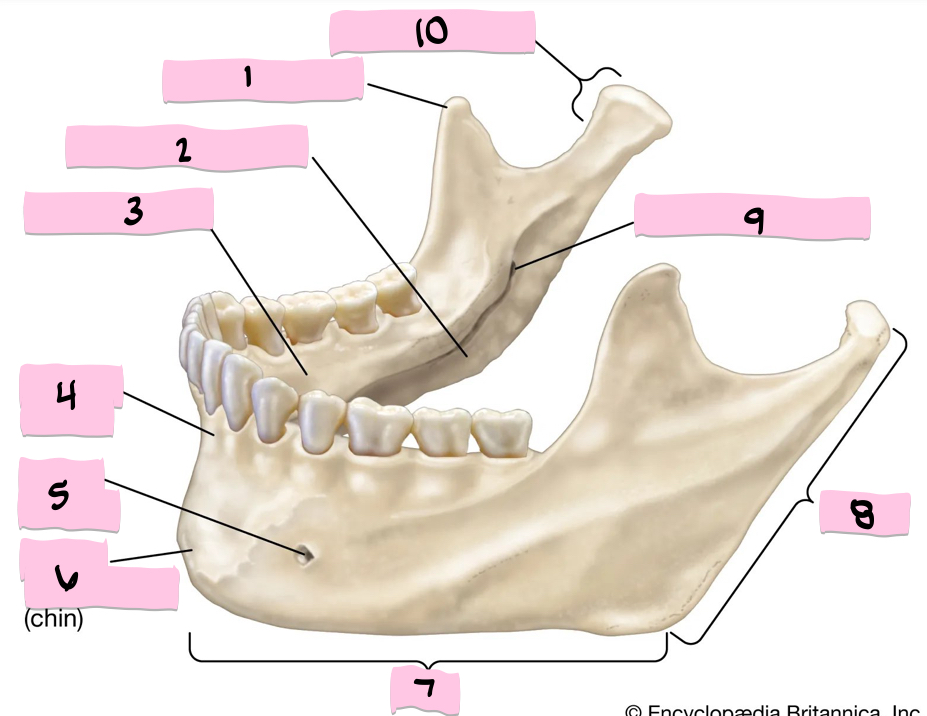

What is 1 pointing to?

Coronoid process

What is 2 pointing to?

Submandibular fossa

What is 3 pointing to?

Sublingual fossa

What is 4 pointing to?

Alveolar process

What is 5 pointing to?

Mental foramen

What is 6 pointing to?

Mental protuberance

What is 7 pointing to?

Body

What is 8 pointing to?

Ramus

What is 9 pointing to?

Mandibular foramen

What is 10 pointing to?

Condylar process